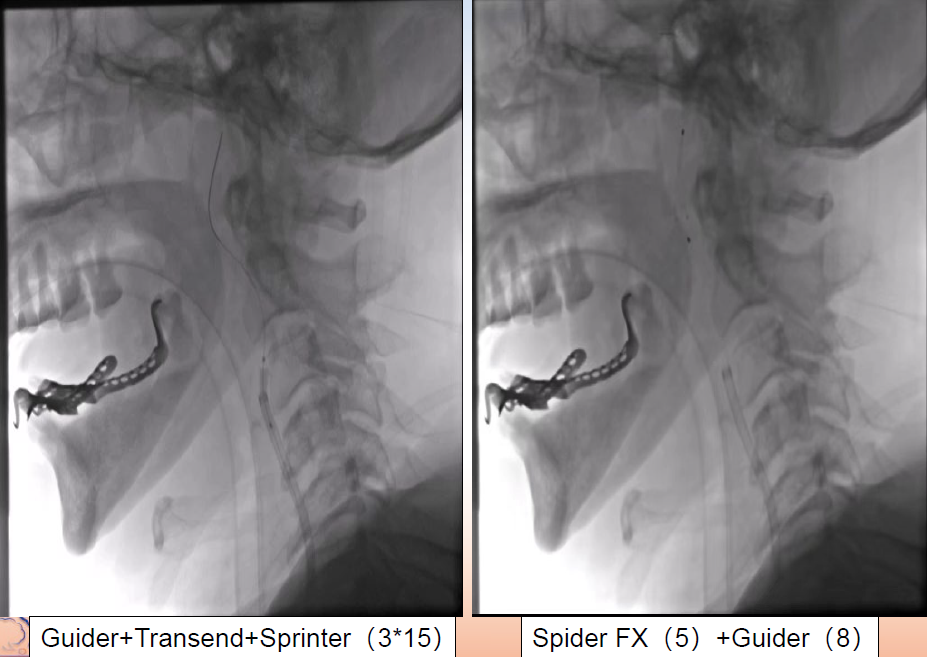

在Synchro微导丝与Rebar-18支架导管的辅助下顺利超选上去,借助Transend导丝使用球囊穿梭技术将Sprinter(3*15)球囊装入血管真腔中。

过程影像

病历夹什么径技·第152期|串联营病历夹:川陕大营_https://www.jmylbn.com_新闻资讯_第83张

病历夹什么径技·第152期|串联营病历夹:川陕大营_https://www.jmylbn.com_新闻资讯_第84张

<<滑动查看下一张图片>>

由于guiding通过失败所以先处理近端,将Spider FX(5)保护伞置入进行了远端保护,近端放置了WALLSTENT支架,然后收伞,顺势将guider通过,结果其无法到达远端。

病历夹什么径技·第152期|串联营病历夹:川陕大营_https://www.jmylbn.com_新闻资讯_第85张

病历夹什么径技·第152期|串联营病历夹:川陕大营_https://www.jmylbn.com_新闻资讯_第86张